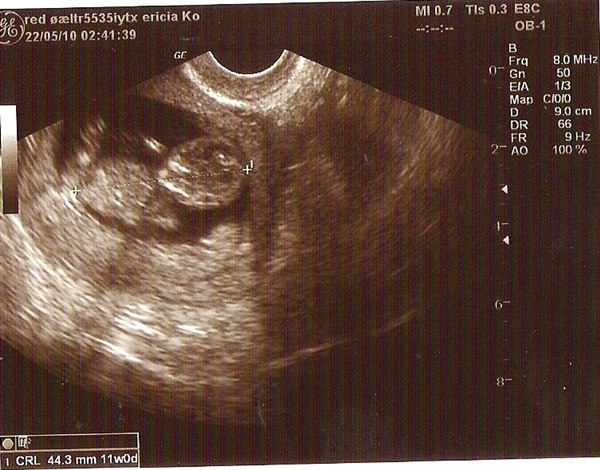

Har det rigtig godt, blødte lidt i går, men det var så lidt så det ikke har slået mig ud af kurs, men er meget obs på hvad kroppen sender af signaler. Var til nf ionsdags, men da den lille ikke ville vende rigtig efter utrolig mange forsøg så fik jeg en ny tid til på torsdag igen.

Kan godt mærke på psyken det tager hårdt når jeg begynder at bløde, det er frustrende jeg ikke ved hvad det er der sker, og om der er liv!!